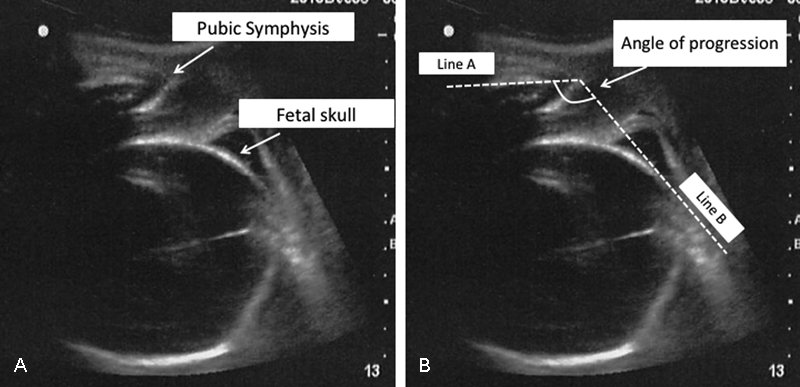

SC Ob/Gyn Society@sc_obgyn·15 KasAngle of Progression on #Ultrasound in the Second Stage of Labor and Spontaneous #Vaginal Delivery ow.ly/JGEM30gqdgO #obgynÇevir English0000

SC Ob/Gyn Society@sc_obgyn·8 KasAngle of Progression on #Ultrasound in the Second Stage of Labor and Spontaneous #Vaginal Delivery ow.ly/JGEM30gqdgO #obgynÇevir English0000